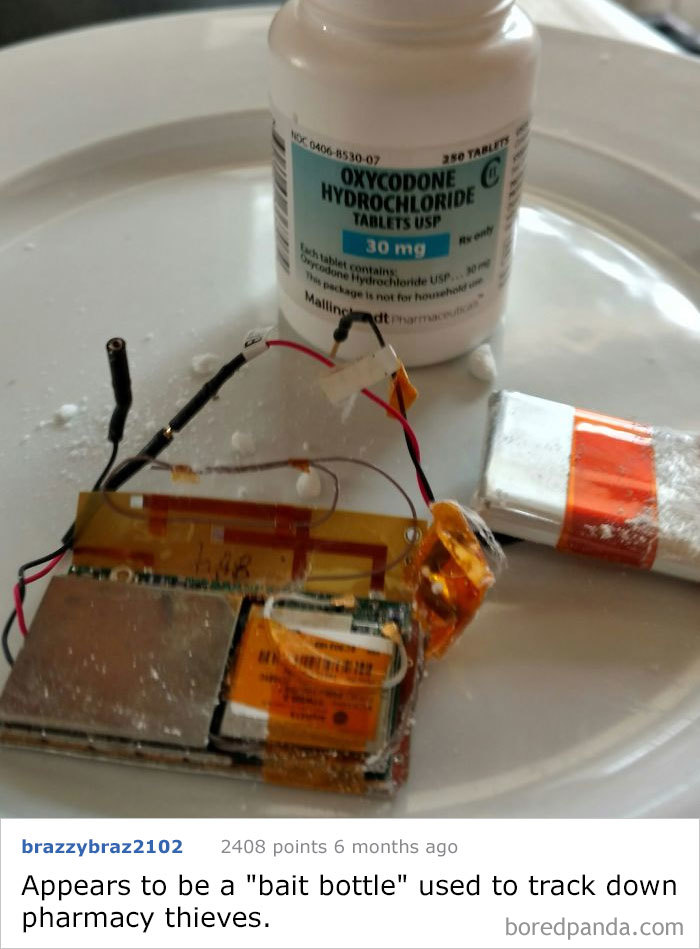

Oxycodone Bottle Found In The Woods With Electronics Inside. What Is This Thing?